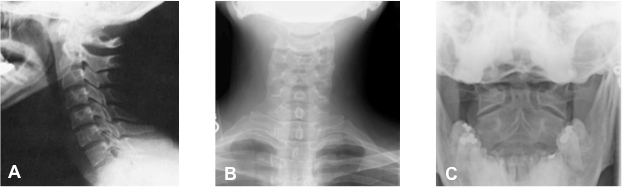

The Cervical Open Mouth View Radiograms A The Cervical Open Mouth Download Scientific Diagram

An Unusual Hangman S Fracture Description And Surgical Management Sciencedirect

Surgical Management Of Axis Traumatic Spondylolisthesis Hangman S Frature